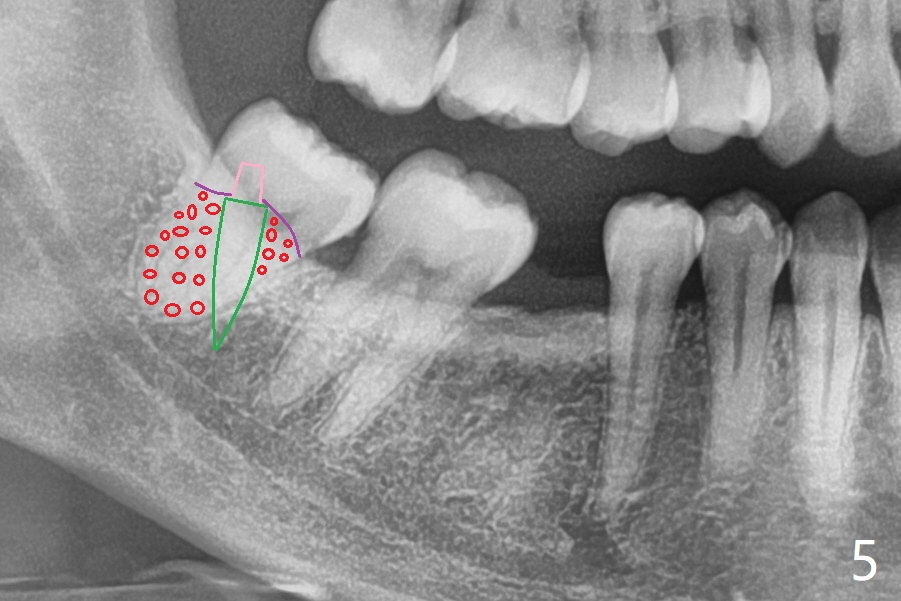

27岁女,小的时候在国内做过牙齿矫正,留下不好印象,不愿意再次矫正。她缺失右下6;7,8明显近中移位(图一,二)。左下7近中颊侧牙尖位于上6,7之间(图三:^),理论上,右下7必须远中移位到8牙位一半(图四)。经过反复讨论(包括前移7,8),病人同意拔除8,做右下后牙区矫正。为了有效7远中移位,拔除8后即刻种植(图五:绿色),植骨(红圆圈),覆盖PRF膜(紫色线)。一旦植牙整合,制作临时牙冠(图六:蓝色;并且提高咬合,这样7有垂直空间后移(直箭头)旋转(弯箭头)),永久性粘固,可能在7,8之间使用power chain,起牵拉作用,棕色方块代表矫正器。一旦6空间扩大,植牙。整合后也可以作为支抗,继续将7远中推移。一定时光,取出智齿植体,完成暂时性支抗作用。